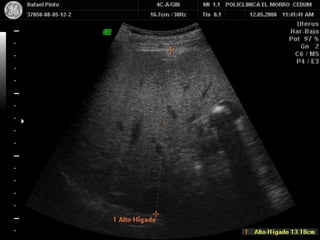

ANATOMIA NORMAL DE LA

VESICULA BILIAR